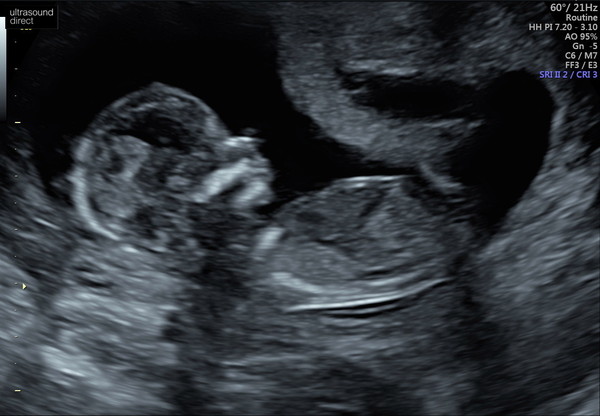

Thanks ladies, reading positive stories kept me going so it’s nice to share mine too. This is the little wriggler here!

@Hoping2020 what a lovely clear scan pic! So pleased that today went well. We aren't going to find out, I feel like there are so few surprises left. Plus I love babies in white, so this way we're more likely to be gifted gender neutral stuff.

TunnocksTcake · 24/03/2020 19:30

Gender guesses welcome!

Aww lovely @TunnocksTcake Smile I’m thinking boy! Are you finding out?

@TunnocksTcake brilliant and beautiful scan photo, it's a girl 😉🌷